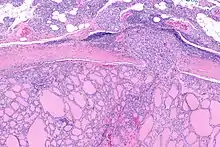

Micrograph of follicular thyroid carcinoma showing a location where the cancer grows through the fibrous capsule. H&E stain.

It is impossible to distinguish between follicular adenoma and carcinoma on cytological grounds. If fine needle aspiration cytology (FNAC) suggests follicular neoplasm, thyroid lobectomy should be performed to establish the histopathological diagnosis. Features sine qua non for the diagnosis of follicular carcinoma are capsular invasion and vascular invasion by tumor cells. Still, focuses of the capsular invasion should be carefully evaluated and discriminated from the capsular rupture due to FNA penetration resulting in WHAFFT (worrisome histologic alterations following FNA of thyroid).